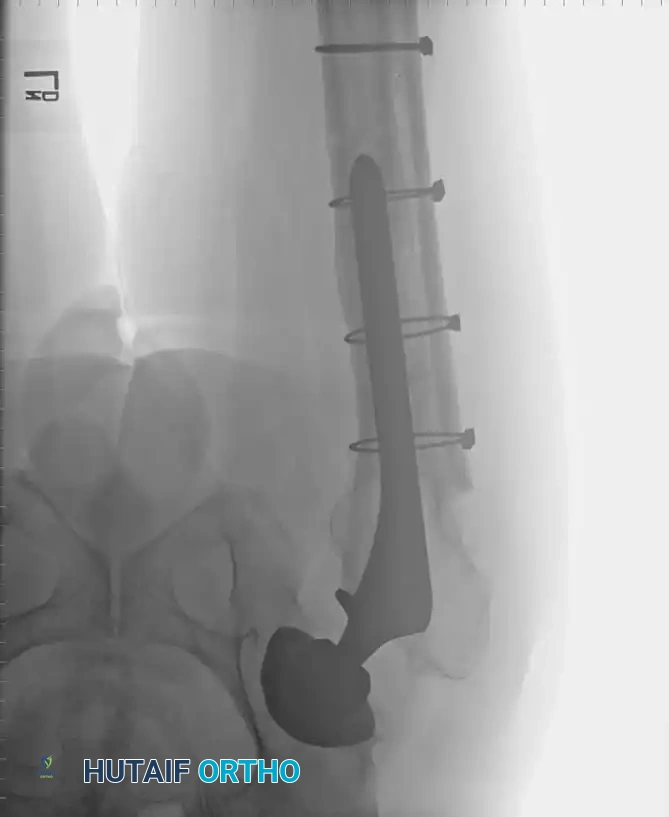

Radiographic Case Examples: Osteoarthritis and Complex Reconstructions

The following imaging series demonstrates various stages of complex acetabular and femoral preparation, highlighting the necessity of restoring offset and center of rotation.

Implant Selection and Fixation

Preparation of the femur is usually straightforward due to a widened medullary canal (Dorr Type C "stovepipe" femur), but the cortices are paper-thin and easily penetrated. The acetabulum is similarly soft, and the medial wall is easily breached during reaming.

While severe osteopenia historically favored cemented fixation, contemporary highly porous cementless components have shown excellent survivorship in RA patients. In patients with JIA, the skeleton is often underdeveloped, necessitating custom or ultra-small components. Excessive femoral anteversion and anterior bowing of the proximal femur are also common in JIA, occasionally requiring a concomitant femoral osteotomy.

Radiographic Case Examples: Inflammatory Arthropathy and Osteopenia Management

Use of a multi-hole cup for enhanced screw fixation in poor bone stock.

Final construct demonstrating stable fixation despite severe osteopenia.

Associated Surgical & Radiographic Imaging

Hutaifortho's Orthopaedic Diagram